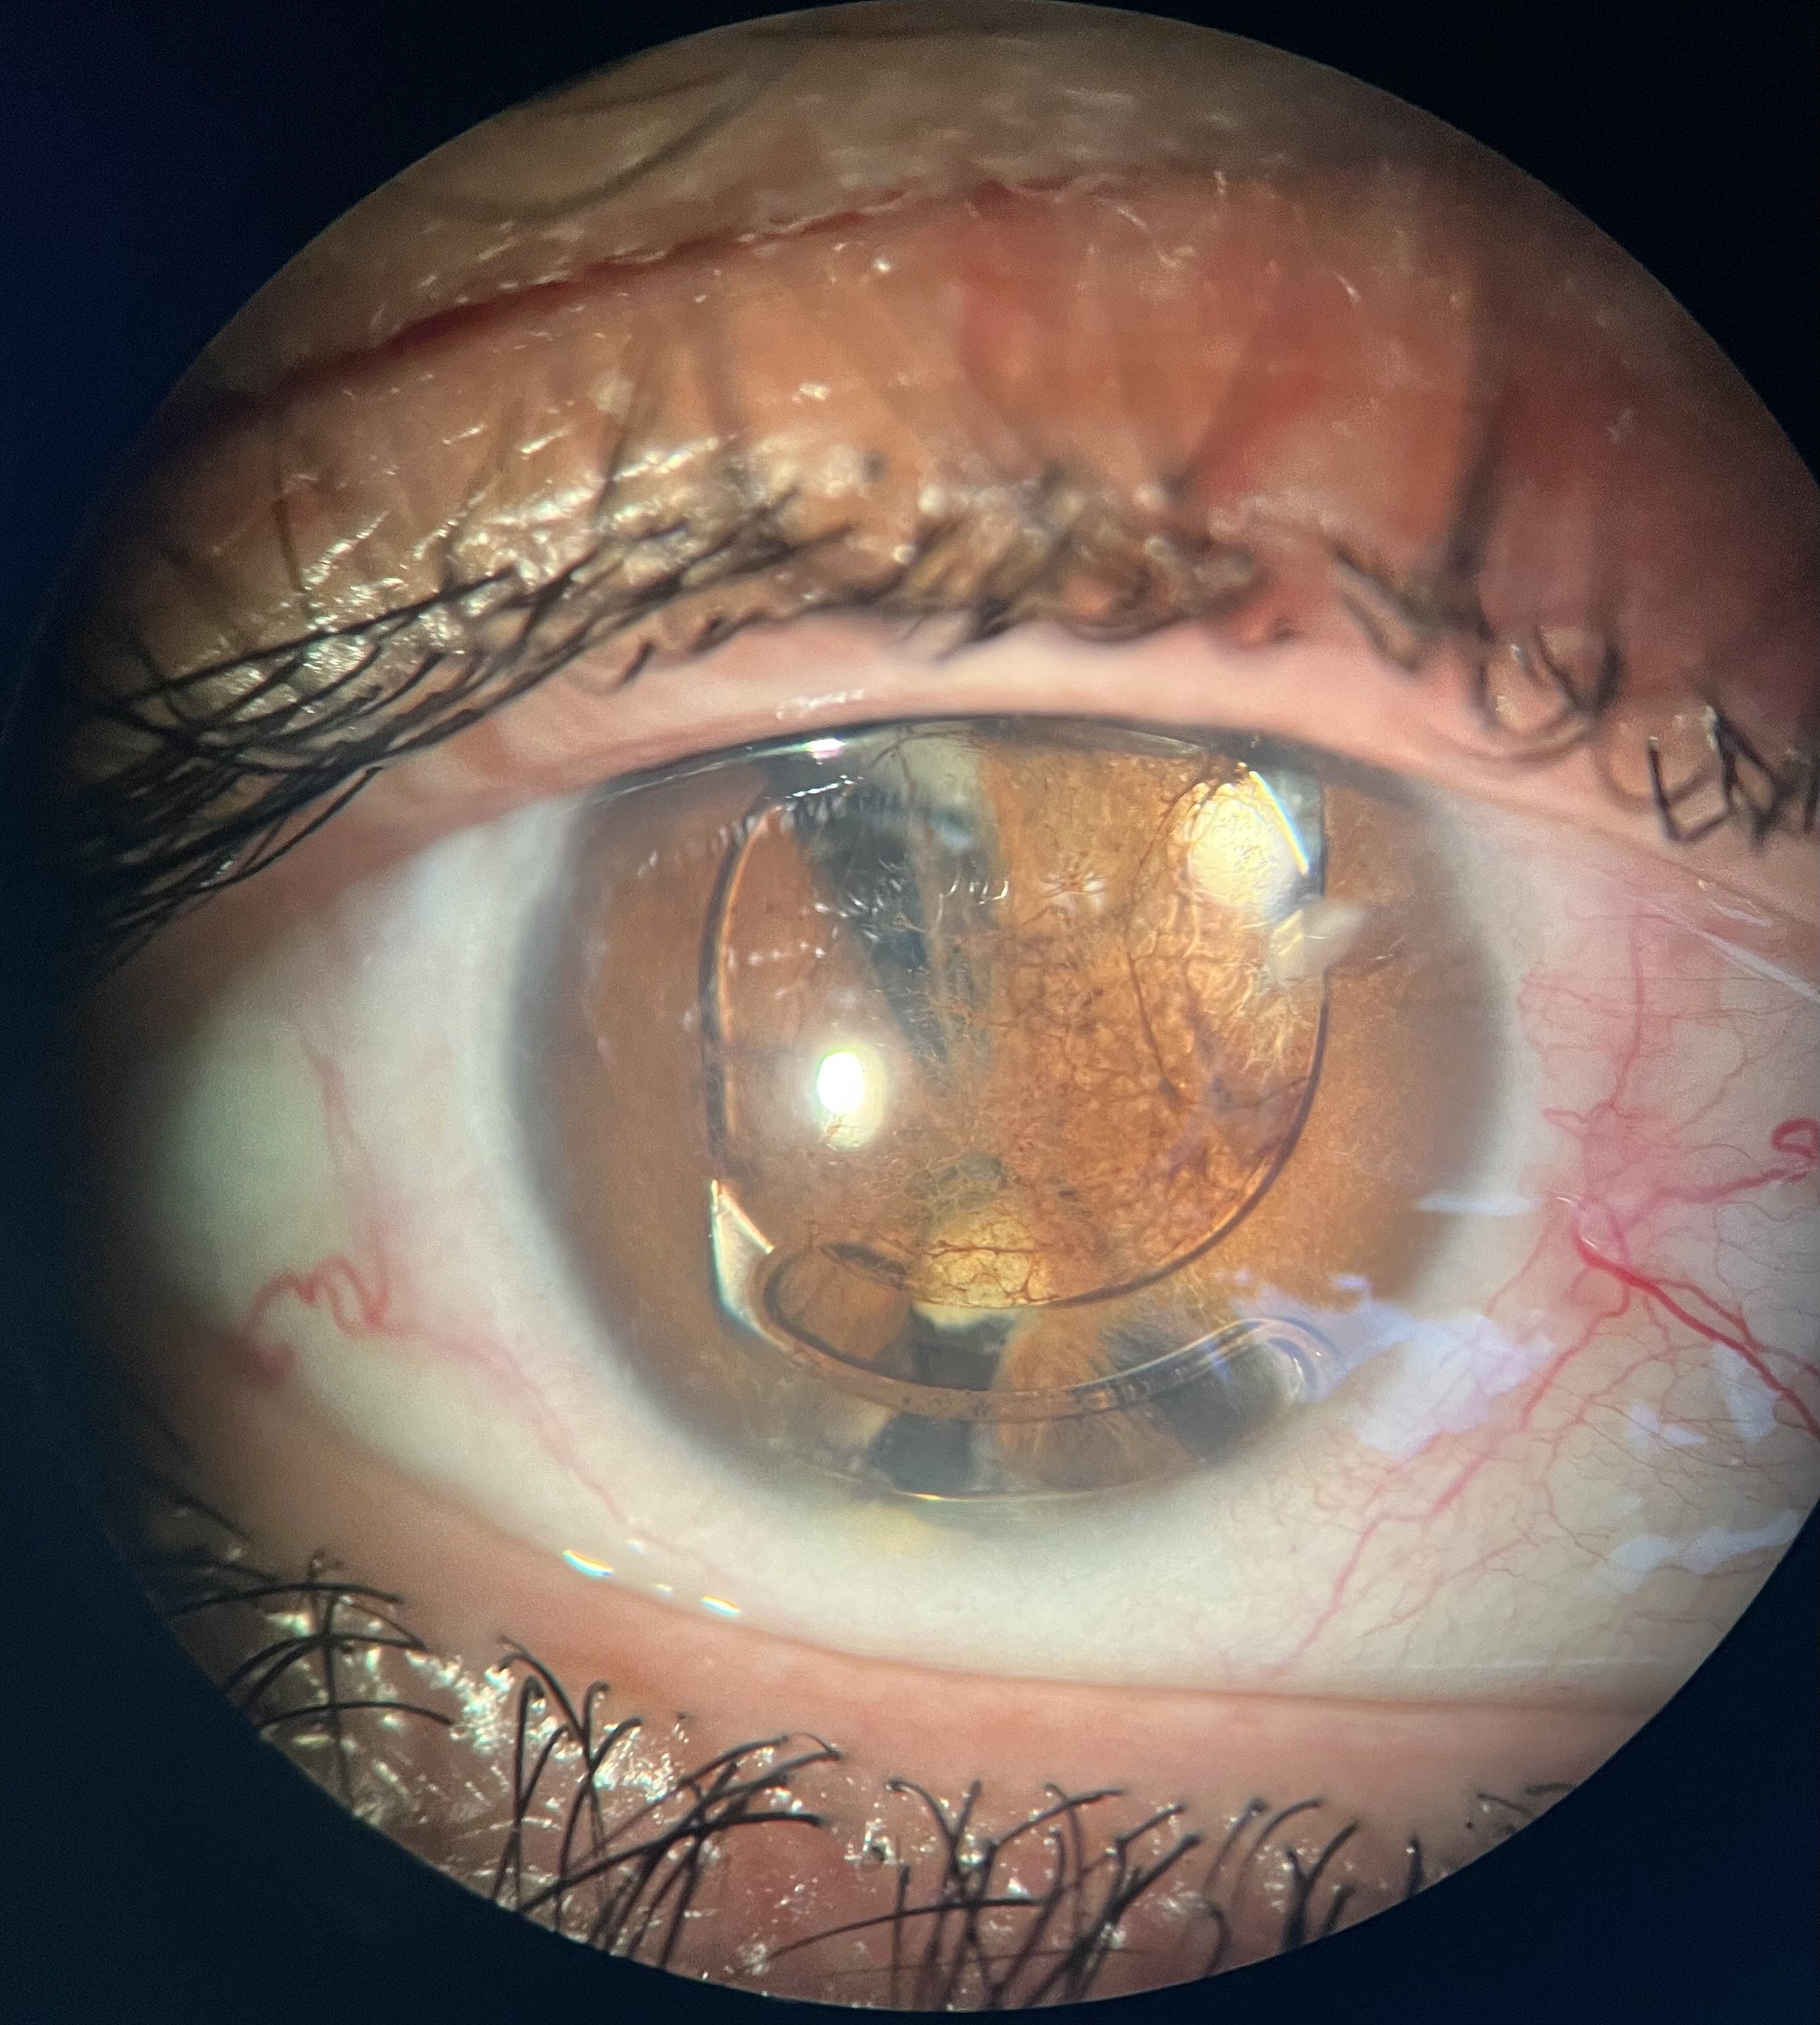

Voici quelques exemples de photos des années passées :